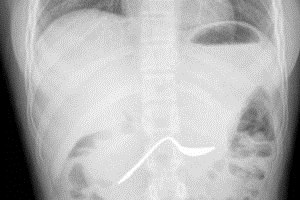

שלום, נראה שיש צלקת מדלקת הריאות שעברת. מומלץ לעשות בדיקת תפקודי ריאות מלאים והערכה במרפאת ריאות עם הסיטי.

שלום, זה לא חד משמעי, במידה שיש תלונות נשימתיות ממליץ לעשות בדיקת תפקודי ריאות וסיטי. הצילום לא מראה מספיק טוב בעיות דלקתיות כרוניות.

שלום, הכוונה שיש שינוי בריאה שיכוצ להעיד על סוג של דלקת ממושכת, לפעמים זה קשור לעישון. מומלץ להשלים בדיקת תפקודי ריאות מלאים ולהגיע להערכה במרפאת ריאות.